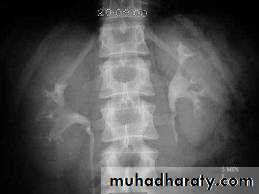

A. First a plain x-ray of the abdomen is taken before the injection of the contrast media, also known as A KUB (kidney, Ureter and Bladder). Calcification & stones may be obscured & missed by contrast media if plain film not takenfirst .B. Films taken after injection of contrast’ medium: